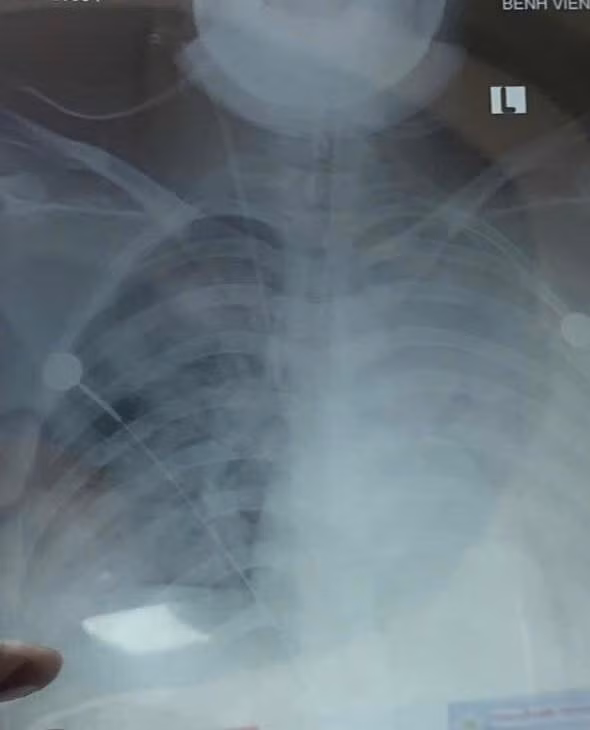

Bệnh nhân nữ, 19 tuổi, nhập viện trong tình trạng khó thở, sốt cao, ho đờm. Chẩn đoán ban đầu là viêm phổi nặng. Chỉ trong vòng 3 ngày, tình trạng hô hấp suy sụp nhanh chóng, hình ảnh X-quang và CT phổi cho thấy phổi trắng xóa hai bên – dấu hiệu điển hình của Hội chứng suy hô hấp cấp tiến triển (ARDS), một biến chứng nguy kịch thường gặp ở những ca viêm phổi nặng.

Hình ảnh tổn thương phổi trên phim chụp - Ảnh BVCC